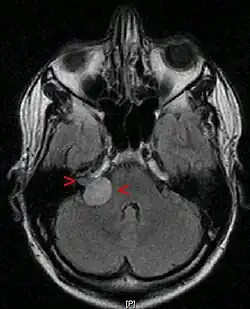

Ein Akustikusneurinom (kurz AKN oder AN) ist ein gutartiger Tumor, der von den Schwann’schen Zellen des vestibulären Anteils des VIII. Hirnnerven, des Hör- und Gleichgewichtsnerven (Nervus vestibulocochlearis), ausgeht und im inneren Gehörgang, bei größerer Ausdehnung auch im Kleinhirnbrückenwinkel gelegen ist. Das Akustikusneurinom ist histologisch eigentlich als Vestibularis-Schwannom zu bezeichnen. Die Bezeichnung Akustikusneurinom ist aber klinisch üblich.[1] Es ist der häufigste Kleinhirnbrückenwinkeltumor.

Diagnose des Akustikusneurinoms

Eine sichere Diagnose liefert nur die histologische Untersuchung nach einer Gewebeentnahme. Erstmals röntgenographisch dargestellt wurden Akustikusneurinome mit Erweiterungen des inneren Gehörgangs durch Salomon Eberhard Henschen (1910) und Hendrik Willem Stenvers (1917).[4] Klinisch relevante Tumoren können heute mit einer Magnetresonanztomographie (MRT) zuverlässig detektiert werden.